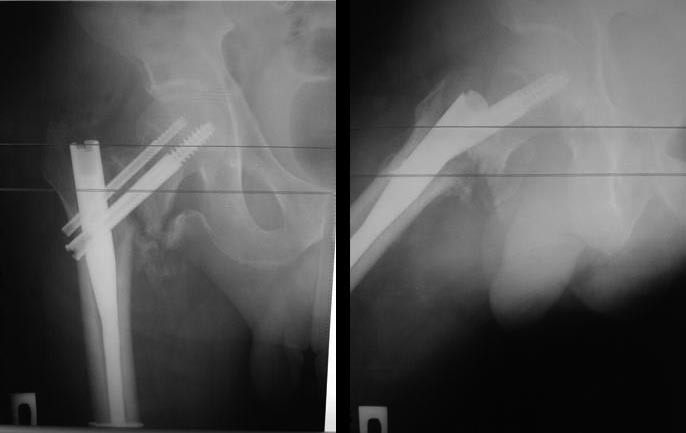

[Ortho] Выполнен остеосинтез Gamma3 1,5 мес назад

результат таков